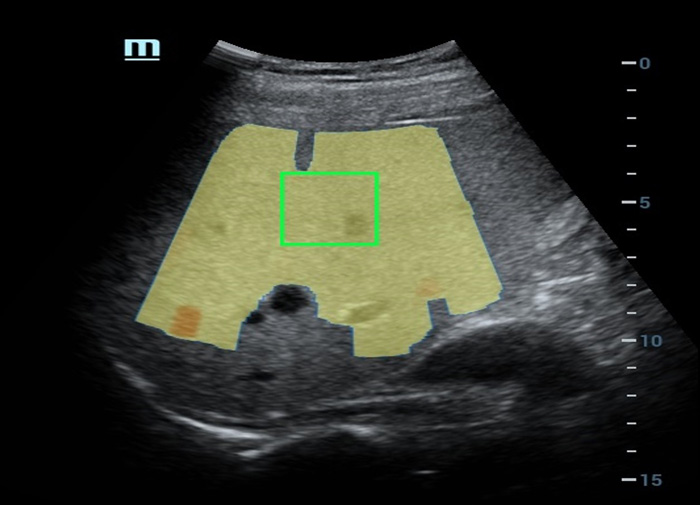

Laboratû°rio multiparamûˋtrico de fûÙgado gorduroso

O laboratû°rio multiparamûˋtrico de fûÙgado gorduroso oferece vûÀrias ferramentas de anûÀlise quantitativa baseadas em diferentes tecnologias. Permite a anûÀlise quantitativa da esteatose e melhora a sensibilidade na detec??o de fûÙgado gorduroso em estûÀgio inicial.

Laboratû°rio multiparamûˋtrico de fûÙgado gorduroso

Um novo salto para a pesquisa sobre esteatose